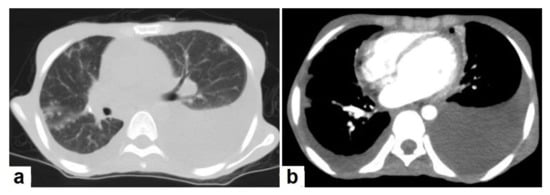

Figure 3. Post primary TB in a 45-year-old male with cough and hemoptysis. Axial images of chest CT show (a) cavitary lesions in the right upper lobe and upper segment of the left lower lobe surrounded with consolidation, (b) cavitary lesion in the upper segment of the left lower lobe with thick irregular wall surrounded by patchy ground glass opacities, (c) centrilobular nodules and tree-in-bud nodules, and (d) consolidation in the left lower lobe with air-bronchograms.

• Consolidation (Figure 3) is considered to be one of the most common features of postprimary TB, which is usually focal, patchy heterogeneous, or poorly defined. It involves the apical and posterior segments of the upper lobes and the upper segments of the lower lobes [10]. Consolidation with ipsilateral enlarged hilar or paratracheal LNs could strongly suggest TB. CT is better able to detect small and subtle TB consolidations, which are usually peribronchial or subpleural and involve multiple lung segments [13].

• Cavitation (Figure 3 and Figure 4) is a common finding in postprimary TB, and it is characterized as being several centimeters in size with thick irregular walls. Cavities are often seen within consolidation and may persist after treatment predisposing to a bacterial or fungal superinfection or adjacent vascular erosion causing hemoptysis [1,10]. In postprimary TB, both consolidation and cavitation have a predilection for the apical and posterior segments of the upper lobes and the upper segments of the lower lobes [1,14]. This predilection of TB is attributed to the relative over-ventilation, high oxygen tension, and delayed lymphatic clearance in these regions [16]. Thick wall cavities are an important differential diagnosis of a pulmonary abscess, septic emboli, aspergilloma, granulomatosis with polyangitis (Wegener’s granulomatosis), lung malignancy, and others [17].

• Centrilobular nodules (Figure 4 and Figure 5) occur due to the communication of active TB with the bronchial tree resulting in endobronchial spread. It occurs in most cases of active TB. It appears as centrilobular nodules and a tree-in-bud sign on CT images [1,10]. The tree-in-bud pattern is seen on high-resolution CT images as 2–4 mm centrilobular nodules of soft tissue density that are connected to multiple branching linear structures of the similar caliber, arising from a single stalk. It commonly occurs in the endobronchial spread of TB and is highly suggestive of active TB. However, a tree-in-bud is a CT manifestation of the diverse entities of lung diseases, including TB, cytomegalovirus, respiratory syncytial virus, obliterative bronchiolitis, diffuse panbronchiolitis, cystic fibrosis, airway-invasive aspergillosis, allergic bronchopulmonary aspergillosis, and pulmonary metastasis [18].